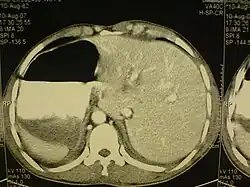

Cet état touche toutes les grandes structures de la cavité thoracique et de l’abdomen. En général, les organes sont simplement transposés par rapport au plan sagittal[1]. Le cœur est situé sur le côté droit du thorax, l’estomac, la rate sur le côté droit de l'abdomen et le foie, ainsi que la vésicule biliaire sur le côté gauche. Le poumon gauche est formé de trois lobes, le poumon droit de deux lobes, tandis que les vaisseaux sanguins, les nerfs, les vaisseaux lymphatiques et les intestins sont également transposés.

Si le cœur est déporté sur le côté droit du thorax, il s’agit d’une anomalie connue sous le nom de situs inversus avec dextrocardie ou situs inversus totalis. Si le cœur reste dans sa position normale, la partie gauche du thorax, il s’agit d’une affection beaucoup plus rare (1 sur 22 000 personnes dans la population générale), désignée par le terme situs inversus avec lévocardie ou situs inversus incompletus. Les personnes atteintes de situs inversus avec lévocardie ou de dextrocardie sans situs inversus présentent des taux beaucoup plus élevés de malformations congénitales que celles qui sont affectées de situs inversus avec dextrocardie. De plus, les individus atteint de cette malformation avec une lévocardie sont des cas qui s'accompagnent souvent de troubles cardiaques[1].